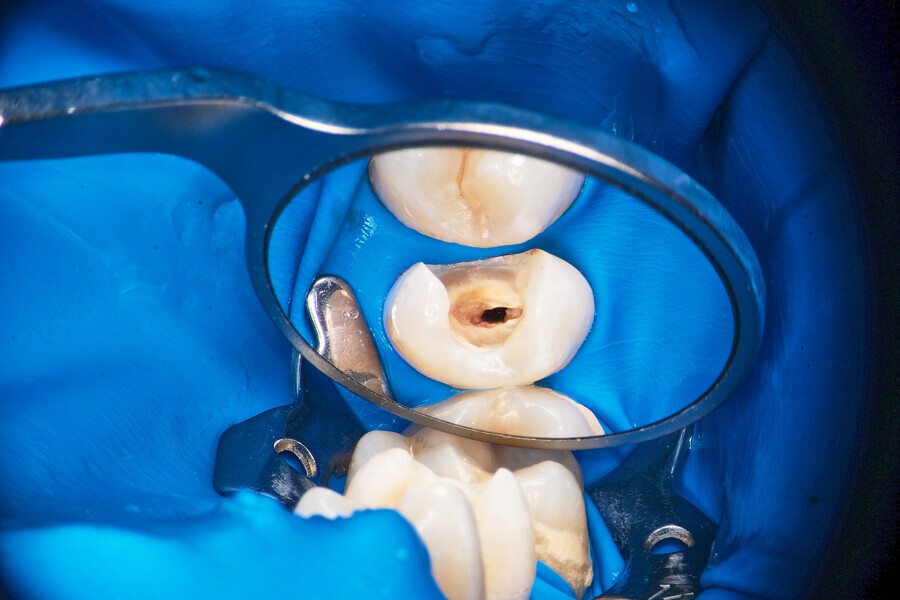

Two treatment plans were presented to the patient, non-surgical root canal retreatment and surgical root canal retreatment. After intra-oral examination, the quality of the prosthodontic treatment was found to doubtful (Fig. 24). The decision was made to remove the crown and perform non-surgical retreatment.

After local anaesthesia, the crown was cut with a high-speed handpiece (Fig. 25). The post was exposed and removed (Fig. 26 & 27). The pulp chamber and root canal orifices were examined for cracks. After inspection, a gingivectomy was performed (Fig. 28) and a dental dam (Kerr Dental) was placed (Fig. 29). The dental dam was sealed with a temporary flowable material (Fig. 30). After sealing the dental dam, the full adhesion protocol with a sixth-generation self-adhesive primer and bonding agent was performed, and the pre-endodontic build-up was created (Fig. 31). Residues of the cement and root canal filling materials were removed with a diamond-coated ultrasonic tip (Woodpecker; Fig. 32). Patency was easily established with hand files (VDW), and the canals were shaped with rotary martensitic files (Poldent) up to 40/0.04. Each step of instrumentation was performed with lubricating cream containing EDTA (VDW; Fig. 33). After each instrument, the canals were flushed with 5.25% sodium hypochlorite (Cerkamed). After reaching the final sizes of the root canals, the irrigation protocol was performed: three sequences of 5.25% sodium hypochlorite and 40.00% citric acid (Cerkamed) activated with an ultrasonic file (MANI), followed by 5.25% sodium hypochlorite activated with the ultrasonic file for approximately 10 minutes (Figs. 34 & 35). The flow of the liquid between both mesial canals was visible.